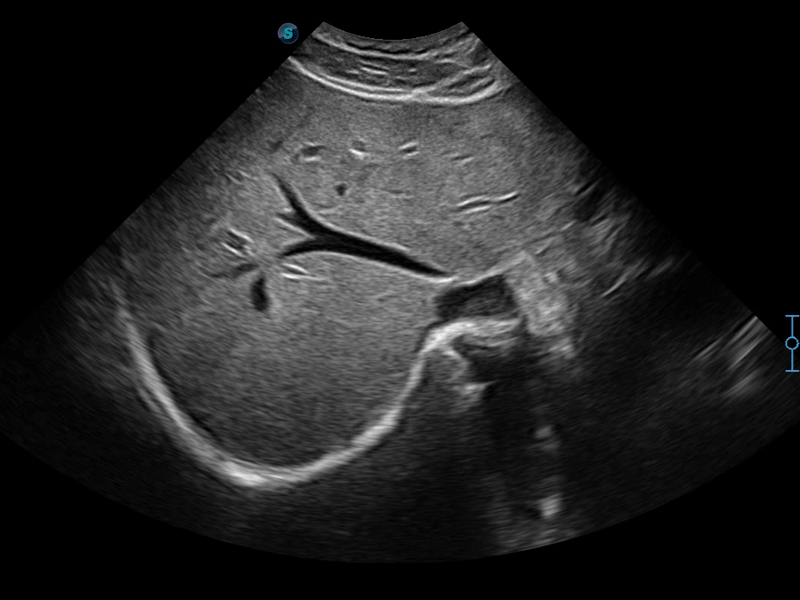

临床图像

μ-Scan+新一代微米成像技术

新一代微米成像技术大大提高了器官和病变的可见性。高清对比度分辨率将抑制斑点噪声,同时保持真实的组织结构。